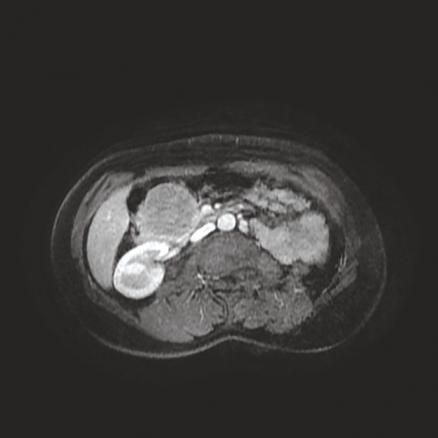

Cette femme de 38 ans était admise aux urgences pour des épigastralgies sans antécédent pathologique notable, avec une fièvre à 38,6 °C ; le bilan biologique mettait en évidence un syndrome inflammatoire sans perturbation du bilan hépatique. La tomodensitométrie abdomino-pelvienne sans et avec contraste réalisée (fig. 1 ) montrait une masse de la tête du pancréas, bien limitée, de 65 x 60 mm, isodense, réhaussée de façon hétérogène, délimitant des zones hypodenses. L’imagerie par résonance magnétique (IRM) pancréatique objectivait une masse de la tête du pancréas en isosignal T1, signal intermédiaire T2, de rehaussement périphérique délimitant une zone centrale liquidienne (fig. 2 ). Une duodéno-pancréatectomie céphalique était réalisée, permettant le diagnostic histologique de tumeur pseudopapillaire et solide du pancréas.

Les tumeurs solides pseudo- papillaires du pancréas sont rares (environ 1 % des tumeurs du pancréas exocrine). Elles surviennent préférentiellement chez les femmes (90 %) jeunes.1 Elles ont un faible potentiel de malignité et peuvent bénéficier d’un traitement chirurgical curatif, mais des récidives sont observées dans 15 % des cas sous la forme de métastases hépatiques ou péritonéales.2 L’IRM est l’examen de choix pour visualiser les composantes kystiques, les remaniements hémorragiques intralésionnels et la présence d’une capsule, sous forme d’un liseré hypo-intense sur les séquences pondérées T2, qui sont caractéristiques de ces tumeurs du pancréas.1 Le traitement est l’exérèse chirurgicale, avec étude anatomopathologique.